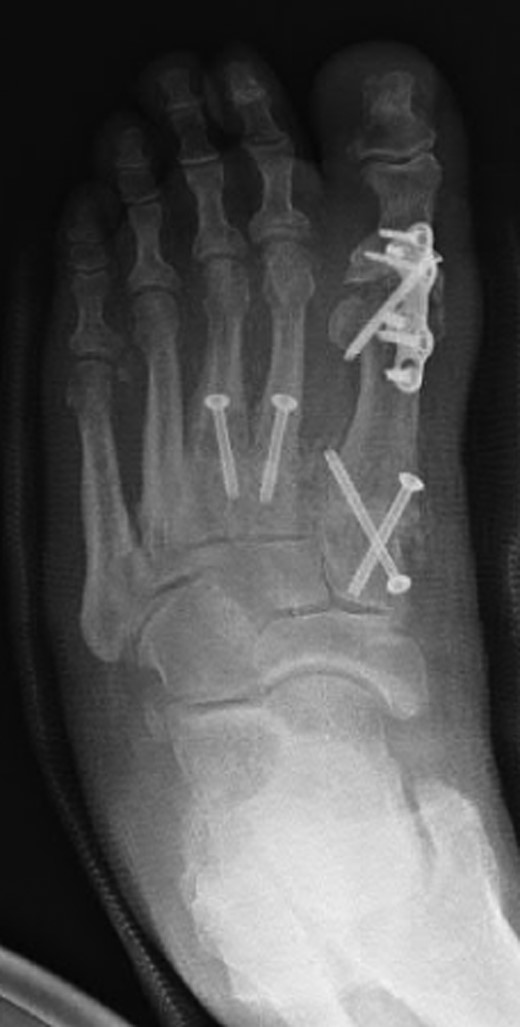

The patient had undergone previous diagnostic and therapeutic corticosteroid injections into his first, second and third TMTJs, temporarily improving the mid-foot pain. The patient wanted complete pain resolution and so underwent arthrodesis of these joints and the first MTPJ (Figs 6 and 7). Operative findings confirmed radiographic findings with the presence of an additional middle cuneiform covered with degenerate cartilage proximally and distally.

Oblique radiograph of the left foot following first MTPJ and first, second and third TMTJ fusions.

Dorsoplanter radiograph of the left foot following first MTPJ and first, second and third TMTJ fusions.

Another clinical significance could arise in the case of a second TMTJ arthrodesis. The dilemma is presented as to whether or not fusion be performed between the second metatarsal base and the additional ossicle (Figs 6 and 7), or to span the additional ossicle fusing the second metatarsal to the middle cuneiform. Either way, careful assessment of the anatomy must be performed preoperatively to ensure that all joint surfaces are prepared and arthrodesed appropriately.